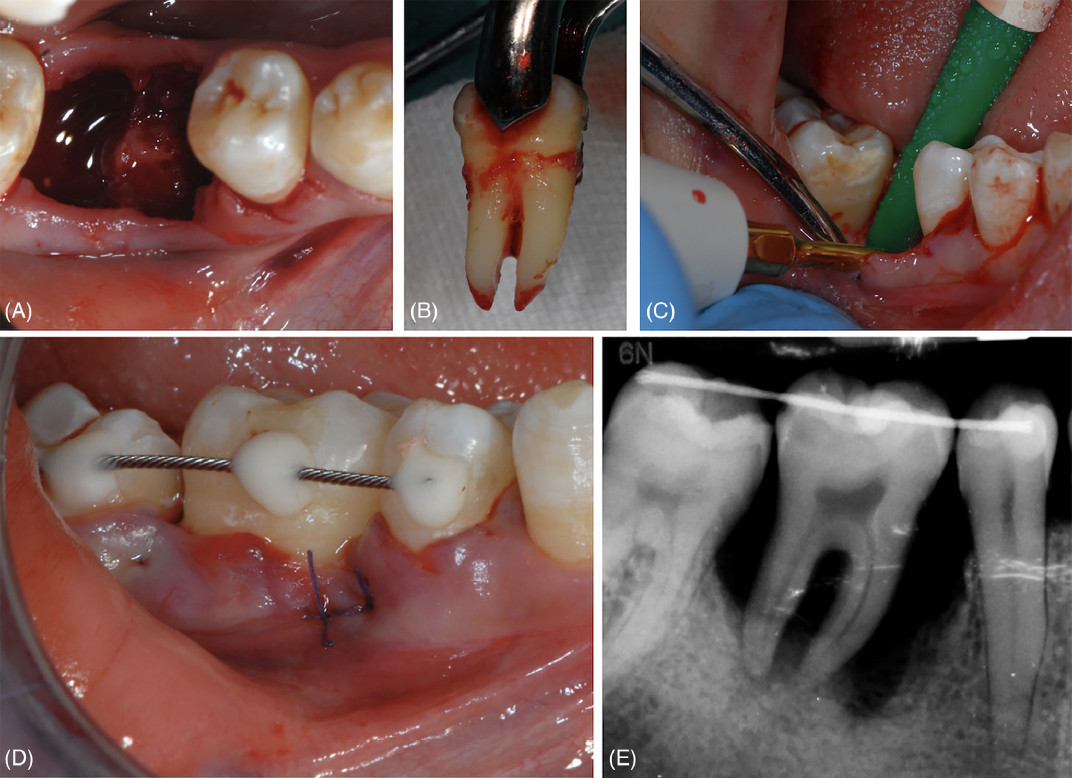

Фото 2. Удаление зуба 46 и его замещение с использованием зуба 48. (A) Лунка после удаления зуба 46. (B) Донорский зуб сразу после его удаления. (C) Остеопластика межкорневой перегородки в реципиентном участке. (D) Клиническая картина сразу после операции и шинирования донорского зуба. (E) Рентгенологическая картина сразу после операции и шинирования донорского зуба

При обеих процедурах использовалась местная анестезия с введением артикаина с адреналином 1:100 000. Удаление зуба 46 выполнялось щипцами после отслойки вестибулярного лоскута; для дегрануляции лунок использовались файлы Гиршфельда. Зуб 48 также был удалён щипцами и промыт стерильным физиологическим раствором. Для адаптации донорского зуба к реципиентному участку потребовалась дополнительная остеопластика. Затем зуб 48 был трансплантирован в РУ с позиционированием цементно-эмалевой границы (ЦЭГ) несколько коронально по отношению к уровню ЦЭГ соседних зубов для лучшей балансировки окклюзионных контактов. Внеальвеолярное время ДЗ составило 7 минут. В заключение вестибулярный лоскут был пассивно репозиционирован и ушит матрасными швами.

Удаление зубов 16 и 18 также выполнялось щипцами; зуб 18 был немедленно трансплантирован в РУ с расположением его ЦЭГ на том же уровне, что и ЦЭГ соседних зубов, после чего был наложен шов.

В обоих случаях для стабилизации ДЗ применялось полужёсткое шинирование зуба (выполненное с использованием композитной смолы с ортодонтической проволокой или без неё), а все окклюзионные контакты были устранены алмазным бором.